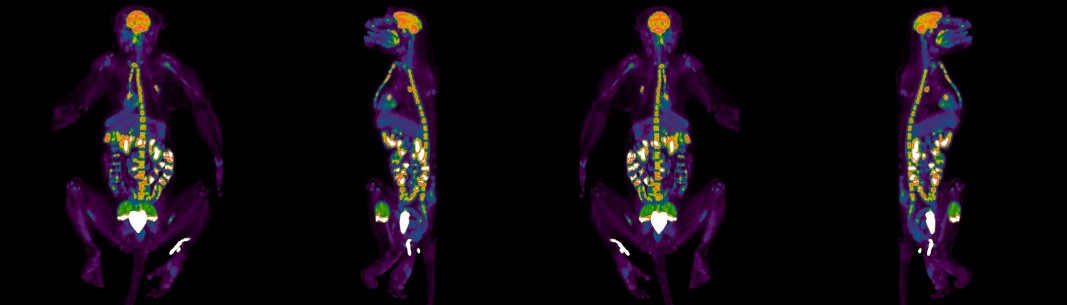

image of the PMIC building and examples of service images

The Primate Multimodality Imaging Center (PMIC) is a comprehensive imaging facility dedicated to state-of-the-art non-invasive imaging.  The center is located in a building designed specifically for in vivo imaging of nonhuman primates with biplane angiography, PET/CT, SPECT/CT, ultrasound, and DEXA, together with support laboratories (wet lab, radionuclide lab). The center is directly adjacent to the ONPRC Magnetic Resonance Imaging (MRI) center, with direct hallway transport to the Animal Services Building (ASB) that houses non-human primates and advanced surgical facilities.